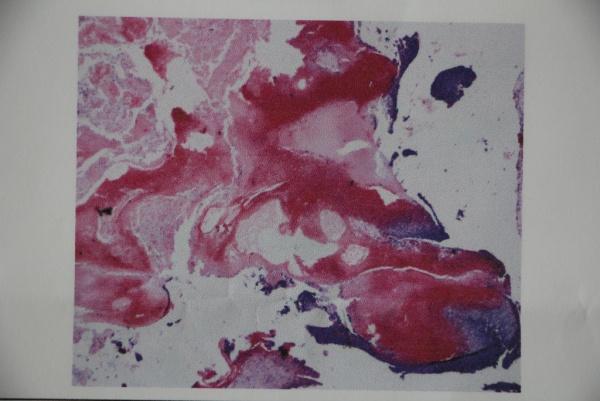

2015年皮肤版有奖病例猜答(36)答案:钙化上皮瘤(毛母质瘤)3人回答准确,已加分。

男,25岁。

右肩部肿物2年余。

查:右肩部可见约1.5X1.8cm大红色隆起结节,触之有囊性感,软骨样硬。

辅助检查:皮肤肿物彩超及病理如下。

答案:毛母质瘤(钙化上皮瘤)。